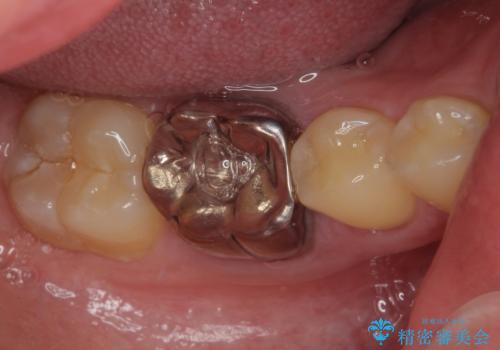

- 銀歯を白くしたいとのことで来院された患者様です。

拡大鏡視野下にて、銀歯を外して、虫歯を除去して、オールセラミッククラウンに適した形に削りました。

型どりはシリコーン印象材にて型どりしています。